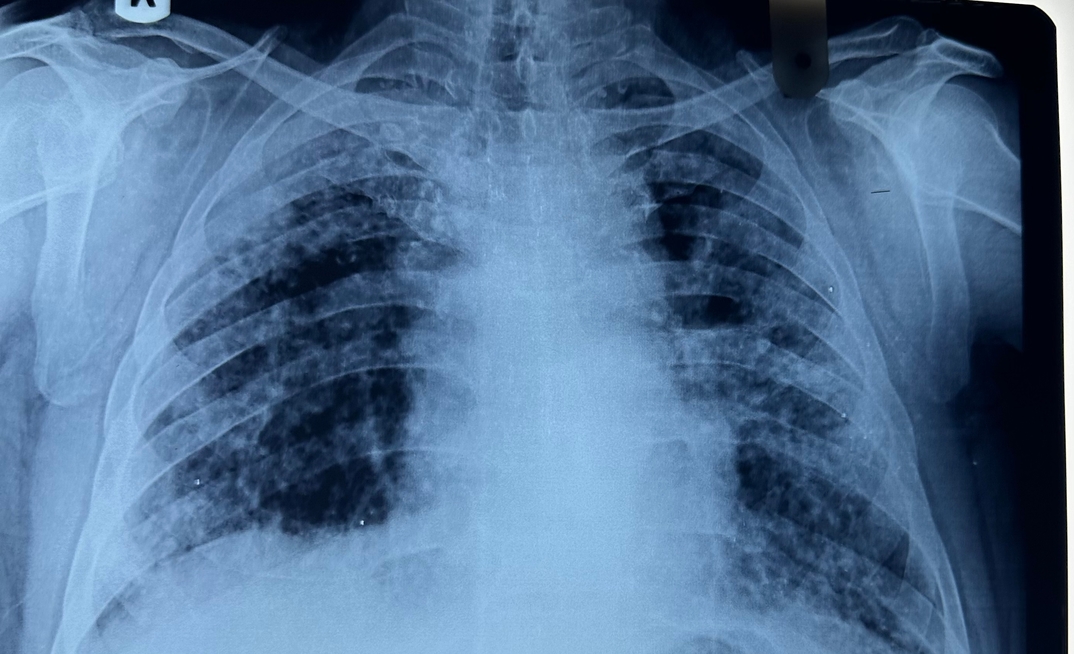

The Tshiamiso Trust is a multi-billion-rand fund set up to compensate miners with tuberculosis (TB) or silicosis, or their families. It was a result of the historic 2018 landmark silicosis settlement....